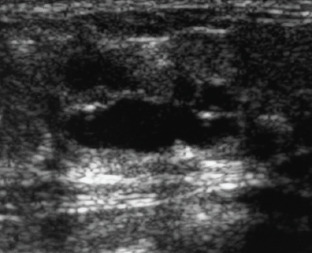

Background: The presence of blood in breast milk gives it a rusty or brownish color, which is referred to as "Rusty Pipe Syndrome (RPS)".

Results: Six women aged 25 to 36, experienced RPS during breastfeeding. The majority of them had no previous birth history (83%), were primigravida (83%) and had bilateral presence of blood in the milk (67%), with symptoms appeared on the second postpartum day (50%).

Conclusion: Based on extensive studies and literature reviews, RPS is generally considered a benign condition, typically presenting bilaterally. However, unilateral cases, such as those observed in our study, are rare.